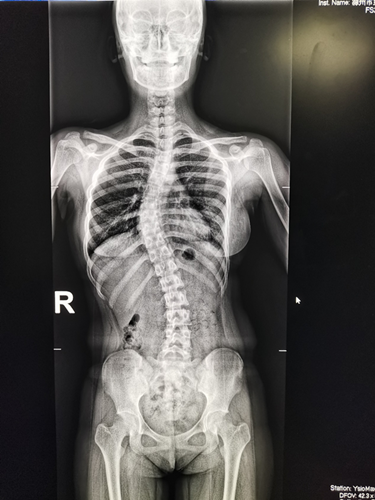

News近日,我院南区放射科首次通过数字影像处理技术获得满意的脊柱全长X光片,为脊柱畸形患者的诊断和治疗提供了重要的影像参考依据。

近年来,因为脊柱畸形问题来骨科就诊的人数增多,脊柱DR摄片只能分部位、分段式成像,医生想要获取患者脊柱全长影像资料,只能一张张读片,十分不便,且拼凑出的脊柱全长影像往往不够准确。而通过数字化图像处理后的脊柱全长正侧位片影像测量可获得相对准确的资料和数据,成为诊断脊柱侧弯最直接、最有效的手段,可以确定畸形的类型、部位,严重度和柔软性。摄片要求患者在站立位下摄脊柱全长正侧位片,以反映畸形的真实情况和躯干的平衡状态,对医生给予患者术前及术后评估提供了主要参考依据。

脊柱侧弯全长正位片 脊柱侧弯全长侧位片

近日,我院南区放射科工作人员在脊柱外科专家、我院朱泽章院长的指导下,通过DR成像系统及拼接软件进行脊柱全长成像技术,将获取的影像资料由图像后处理工作站经过窗宽、窗位调整及拼接软件的处理,形成一幅完整的全脊柱图像。该技术的应用,使人体颈椎、胸椎、腰椎、骶椎显示清楚,图像清晰,为医生的临床治疗工作提供了重要参考依据,还有利于资料保存,值得广泛推广。